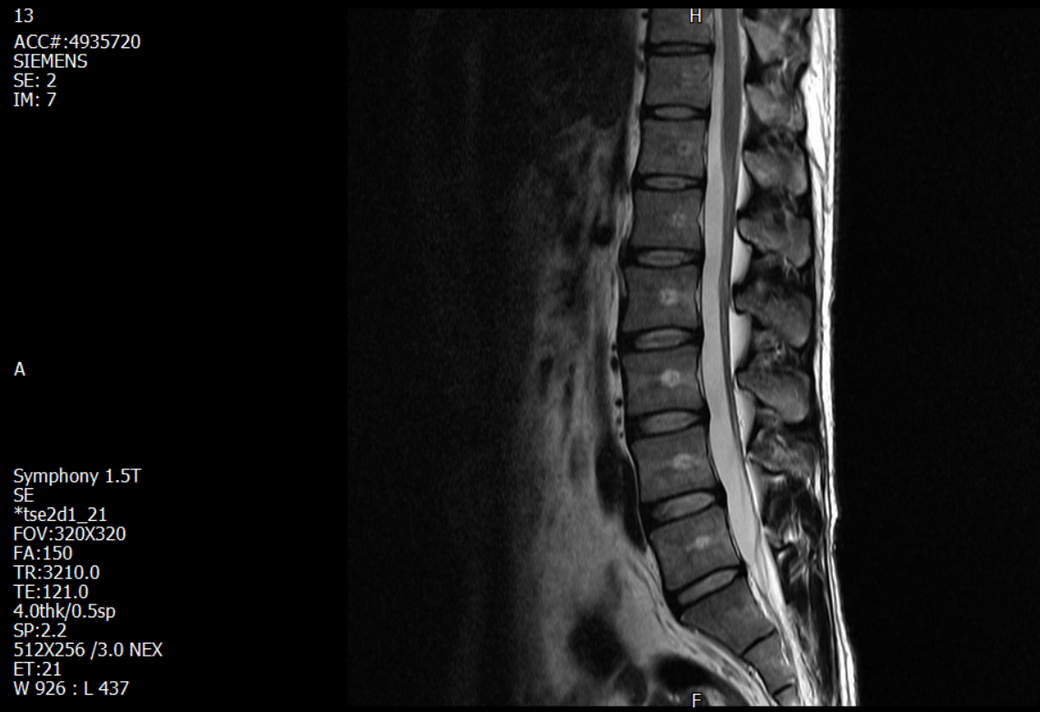

사진은 1년전쯤 찍은 요추 mri 입니다.

본 질문과는 다른 증상으로 촬영했었고 당시 신경외과에서도 요추는 문제없고 건강한 상태라고 했습니다.

• 1번 째 사진